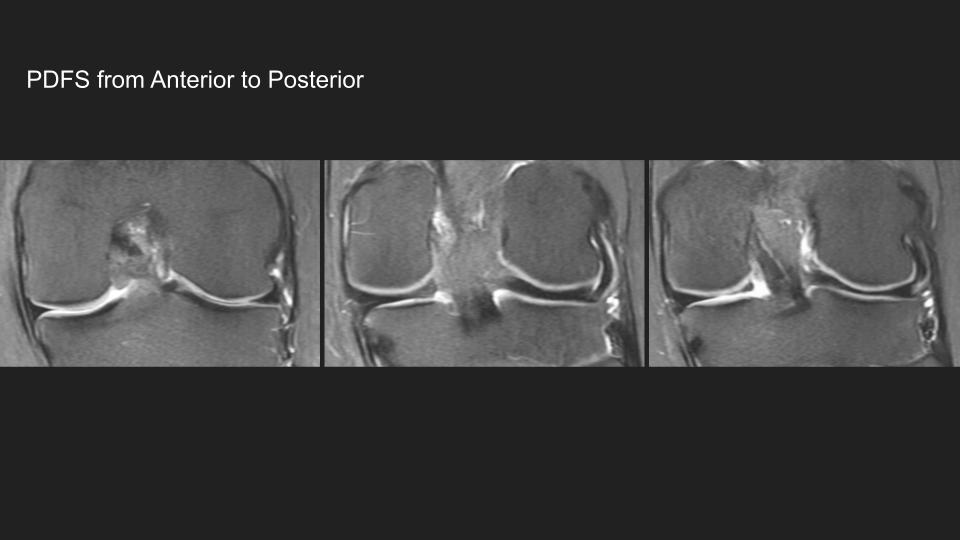

Corresponding PDFS images…useless for seeing the meniscal ossicle, but you see the chronic root tear and the lack of extrusion and the absence of any stress related marrow edema (because it’s chronic)

There is a chronic meniscal ossicle embedded in the stump of the posterior horn medial meniscal root (red arrow) which is chronically avulsed (black arrow)

He got the MRI because he’s symptomatic, obviously, but there is no medial compartment cartilage thinning and no meniscal body extrusion—which is difficult to explain…..can you? What’s providing stability here?